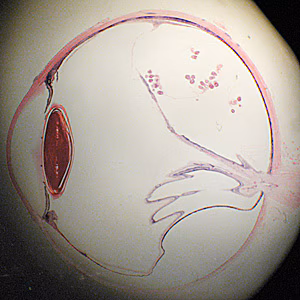

This leads us to the second case for this month. While packing for the move, we discovered an interesting pathology slide labeled with only an accession number. Figure A shows the slide and Figure B shows the specimen using a dissecting microscope. The slide was observed under a compound microscope for higher magnification; Figures C and E show areas captured at 40x, and Figures D and F at 200x. What is your diagnosis? Based on what criteria?

Figure B